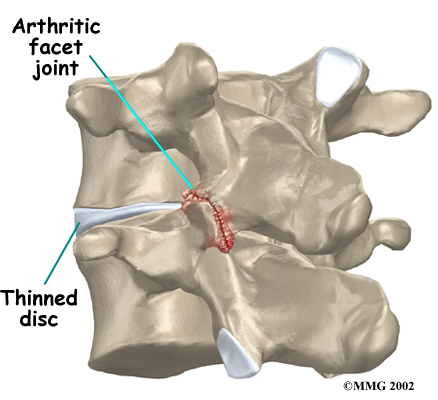

Normally, the facet joints fit together snugly and glide smoothly, without pressure. If pressure builds where the joint meets, the cartilage on the joint surfaces wears off, or erodes.

Each segment in the spine has three main points of movement, the intervertebral disc and the two facet joints. Injury or problems in any one of these structures affects the other two. As a disc thins with aging and from daily wear and tear, the space between two spinal vertebrae shrinks. This causes the facet joints to press together.

Facet joints can also become arthritic due to a back injury earlier in life. Fractures, torn ligaments, and disc problems can all cause abnormal movement and alignment, putting extra stress on the surfaces of the facet joints.

The body responds to this extra pressure by developing bone spurs. As the spurs form around the edges of the facet joints, the joints become enlarged. This is called hypertrophy. Eventually, the joint surfaces become arthritic. When the articular cartilage degenerates, or wears away, the bone underneath is uncovered and rubs against bone. The joint becomes inflamed, swollen, and painful.

Animation of facet arthritis

Facet joint arthritis develops slowly over a long period of time. This is partly because spinal degeneration in later life is the main cause of facet joint arthritis. Symptoms rarely develop immediately when degeneration is causing the problems. However, rapid movements, heavy twisting, or backward motions in the low back can injure a facet joint, leading to immediate symptoms.